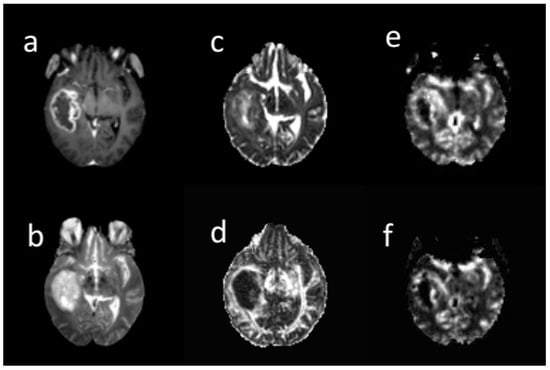

Three extracted clusters within post-contrast T1 tumor images included the contrast-enhanced (CE), non-enhanced (non-en), and necrotic. Two clusters including low mean diffusivity (LMD) and high mean diffusivity (HMD) were extracted on the MD tumor map. A low MD cluster was obtained from the lower MD voxels. The low rCBV (LrCBV) cluster was obtained from the lower rCBV voxels (Figure 2). Based on the overlapping different regions, LMD-LrCBV ROI was yielded within the CE region. Moreover, LMD-LrCBV ROI in necrosis region was extracted. A common area between high mean diffusion and low perfusion was defined as HMD-LrCBV within the necrosis ROI.

Figure 2. A sample of different brain MRI images: (a) post-contrast T1-weighted, (b) T2-weighte, (c) MD map, (d) FA map, (e) CBV map, (f) CBF map in 66-years-old woman with glioblastoma. All images are co-registered to the B0 DTI images. The tumor region was segmented into contrast enhanced, non-enhanced, necrosis in post-contrast image, low and high diffusion in MD map, and low and high perfusion in rCBV map by k-means. Based on their overlapping, sub-regions were obtained.